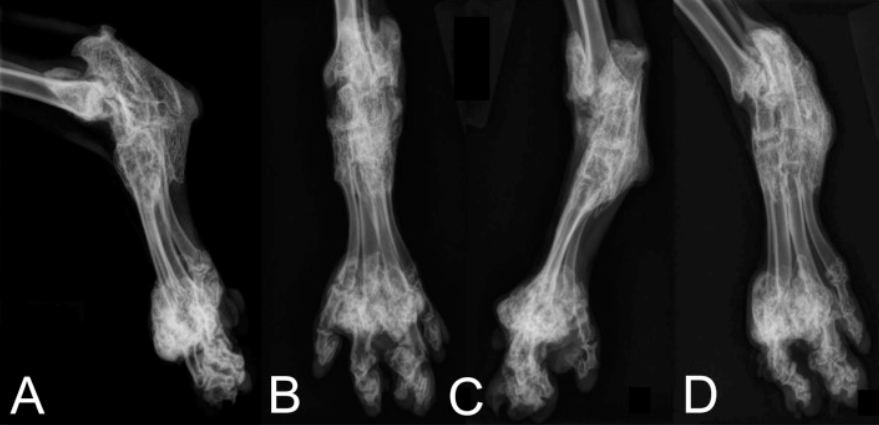

골연골 이형성증이 스코티쉬 폴드 유전병이라 불리는

스로티쉬 폴드라는 종에 유독 많이 발생하는 병인데요.

이 병은 뼈와 연골이 이형성되는 병으로 주로 꼬리,

척추, 발바닥, 사지 말단부에 뼈혹이

생기는 것이 특징입니다.

위 사진은 골연골 이형성증으로

사지말단부에 뼈혹이 과증식 된 모습입니다.

너무 끔직하고 아플 것 같지 않나요 ㅜㅜ